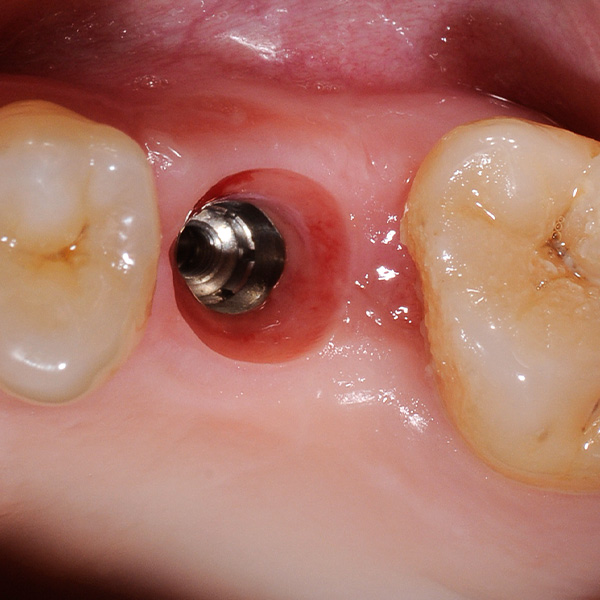

Reconstrucción de corona implantosoportada de cerámica híbrida VITA ENAMIC multiColor

Sobre todo las restauraciones sobre implantes están sometidas a elevadas solicitaciones. Tras la extracción y el implante, al paciente le falta el tejido fibroso elástico del lecho dental natural. En consecuencia, no se absorben las fuerzas oclusales, sino que se transmiten directamente a la restauración, al implante, al hueso y a los dientes antagonistas. La cerámica híbrida VITA ENAMIC incorpora una matriz dual de cerámica (86 % del peso) y polímero (14 % del peso). Esto le otorga una elasticidad similar a la de la dentina y la capacidad de absorber fuerzas oclusales. Gracias a su elevada dimensión vertical, la pieza en bruto policroma VITA ENAMIC multiColor en la geometría EMC-16 posibilita, incluso en caso de hueso atrofiado, la confección de coronas sobre pilar monolíticas de una pieza. El doctor y catedrático Alexander Hassel muestra en el siguiente artículo cómo ha tratado a una paciente empleando este método de restauración.